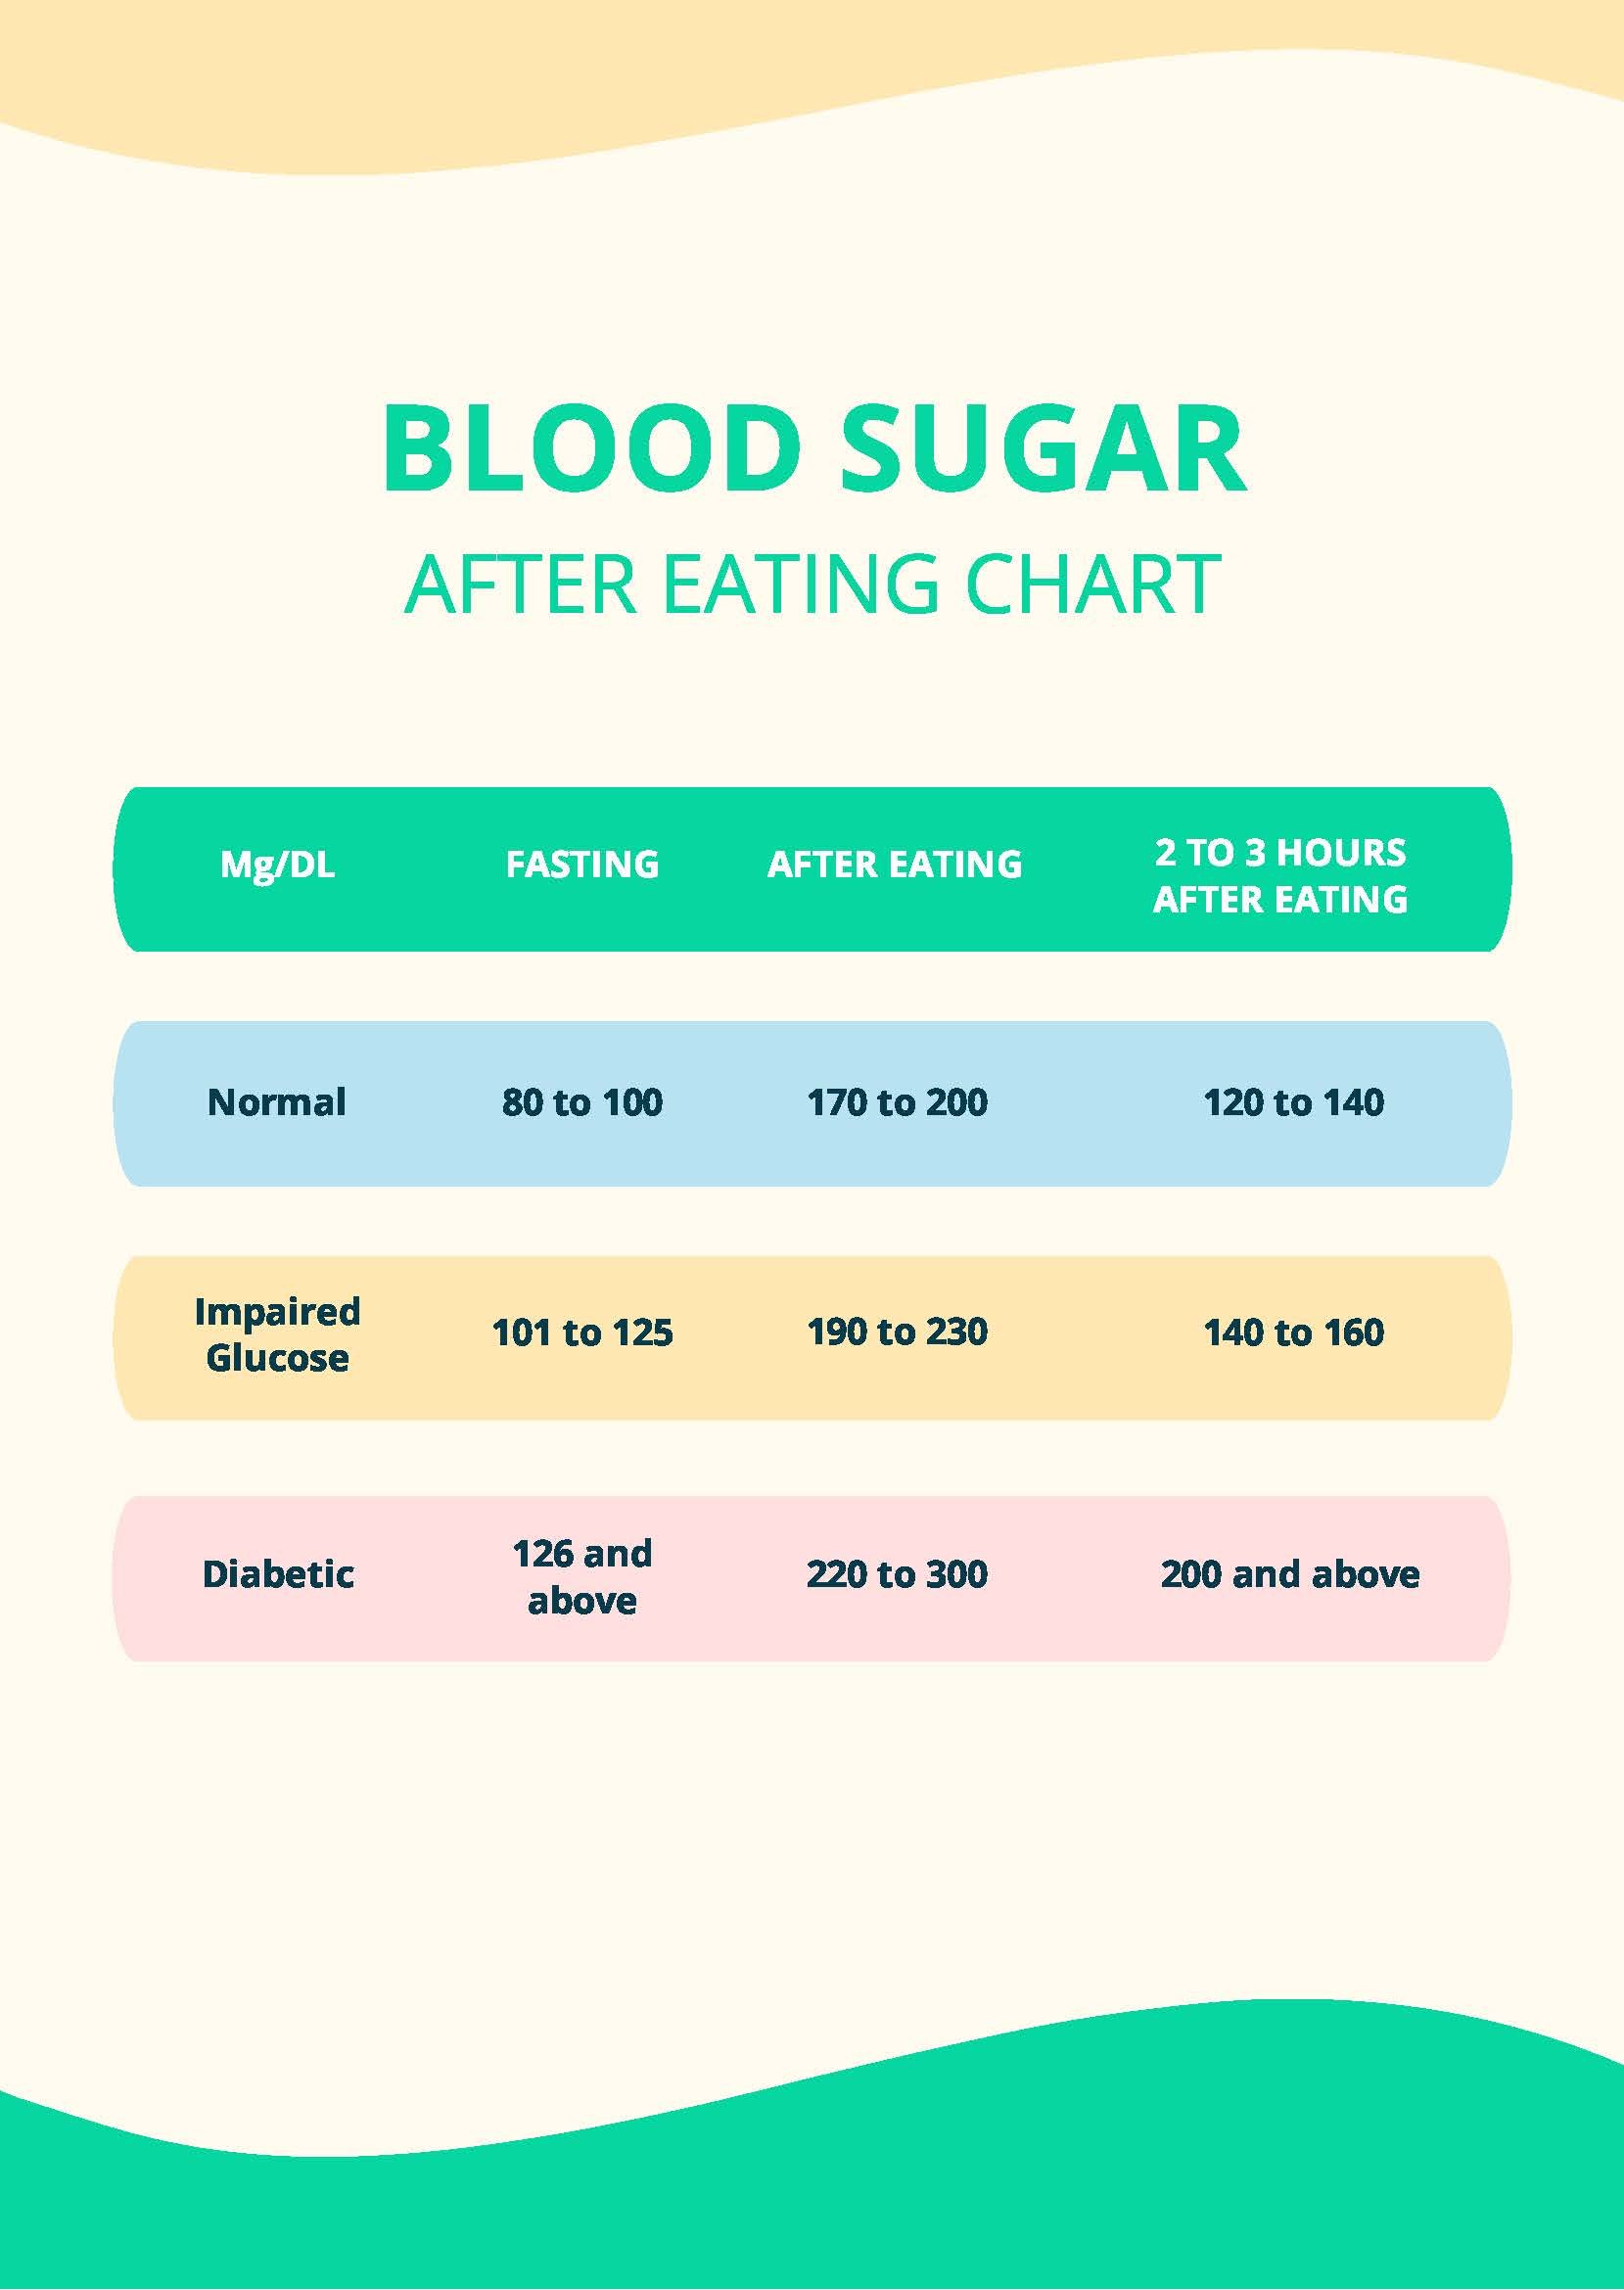

Blood Sugar After Eating Chart In PDF Download Template

Blood Sugar After Eating Chart In PDF Download Template